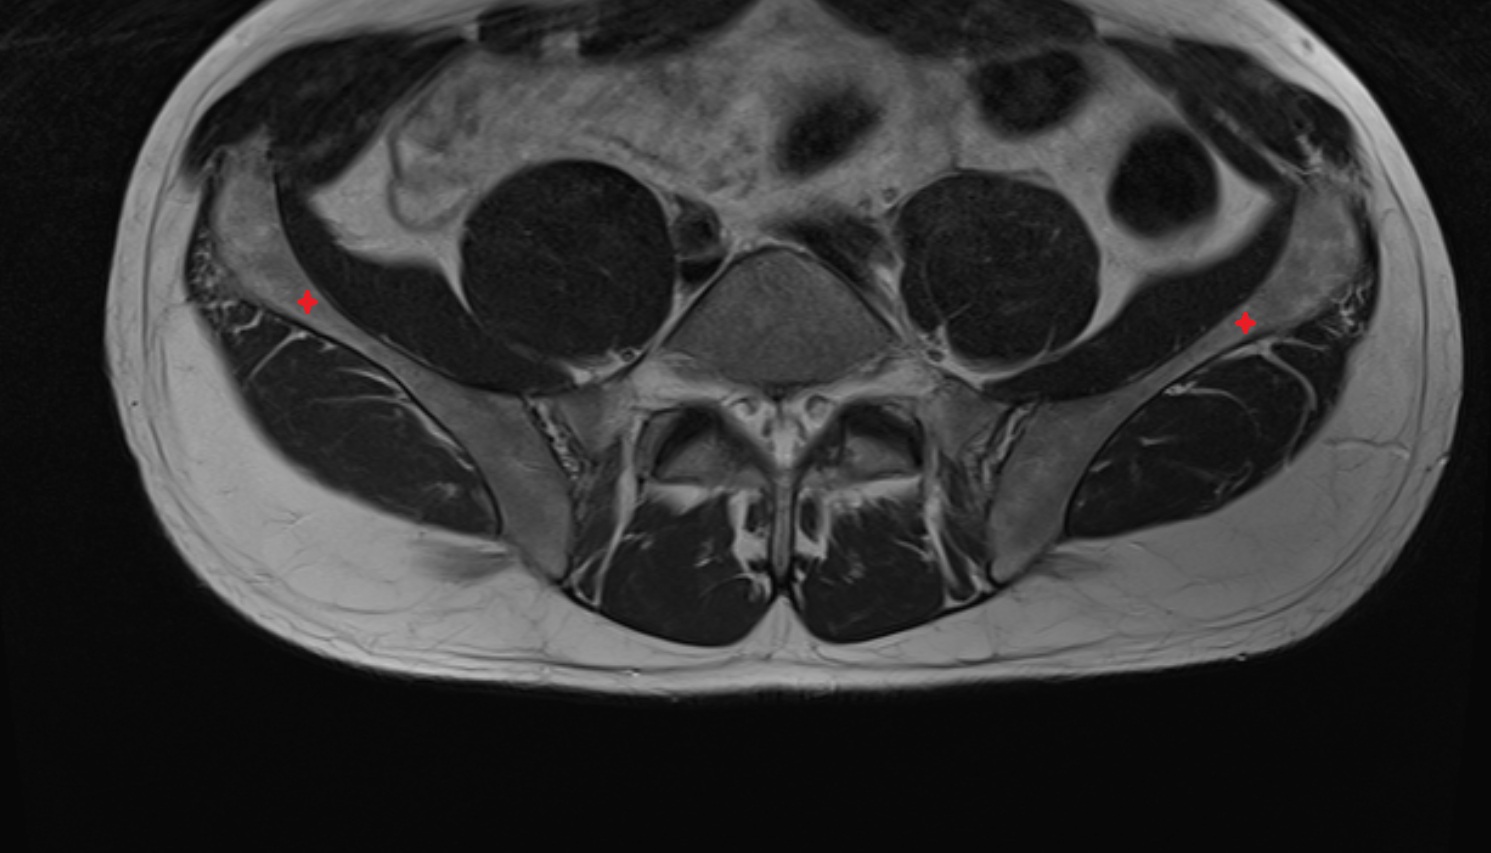

- Sciatic nerve

- External iliac artery

- Femoral artery

- External iliac vein

- Femoral vein